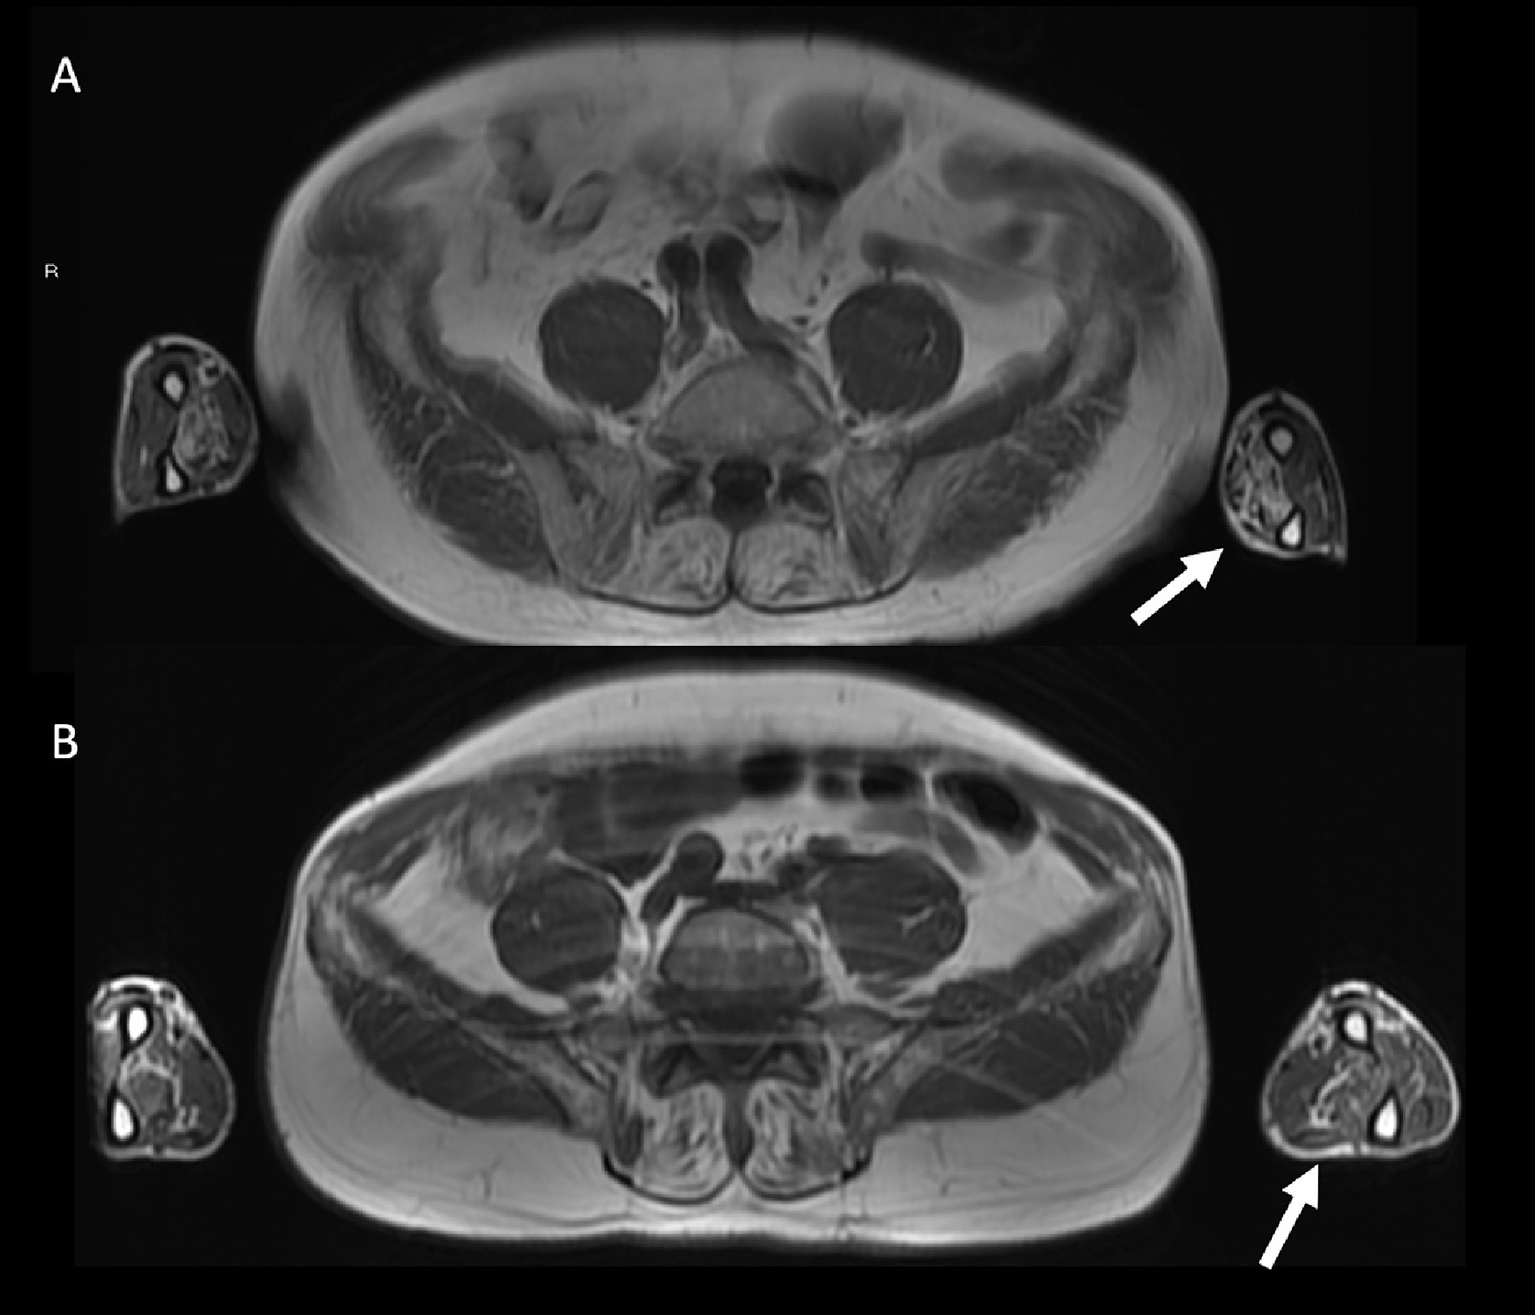

Axial fast spin-echo T1-weighted Whole-Body Muscle Magnetic Resonance Imaging (WBMRI) in a 78 year-old male with inclusion body myositis (IBM) shows moderate-severe fatty infiltration in the flexor digitorum profundus muscles bilaterally (A). A 62 year-old male with inflammatory myopathy with mitochondrial pathology (IM-Mito) shows similar imaging appearance with moderate fatty infiltration in the flexor digitorum profundus muscles bilaterally in axial fast spin-echo T1-weighted WBMRI (B).

Other general radiological findings are shown in Table 7. Muscle edema in at least one muscle was found in most patients with IM-Mito and IBM (Figure 5), but there was no significant difference between the two groups. The mean number of muscles with edema per patient was also similar between the two groups. Asymmetry was observed in most study participants; however, there was no statistically significant difference between patients with IM-Mito and IBM. Most participants with IM-Mito and IBM showed relatively spared rectus femoris muscle compared to other quadriceps muscles (Figure 4). Nevertheless, no statistically relevant difference was found between the groups. The most compromised upper limb muscle by edema or fatty infiltration in patients with IM-Mito and IBM was the flexor digitorum profundus (Figure 6). Although not statistically significant, there was a trend towards greater radiological involvement of these muscles in individuals with IBM compared to those with IM-Mito (100% vs. 64.3%, respectively, p = 0.05).

Our results showed some similar radiological muscle MRI features in patients with IM-Mito and IBM. Most of the muscles evaluated showed comparable presence of edema or fatty infiltration in patients with IM-Mito and IBM. Our study showed a trend towards more muscles being affected by fatty infiltration in patients with IBM compared to IM-Mito. Similarly, a previous study evaluating WBMRI showed that the average mean degree of fatty infiltration and proportion of affected muscles per patient appeared to be higher in IBM compared to IM-Mito (16). Muscles with the highest mean degree of fatty infiltration were quadriceps and medial gastrocnemius in our study’s IM-Mito and IBM groups. It is relevant to mention that distal involvement of the vastus intermedius and medial quadriceps muscles on MRI is considered a typical imaging pattern of IBM (15, 22, 23). Additionally, several publications report medial gastrocnemius as the most consistently affected leg muscle in patients with IBM (23–27). In a study that evaluated WBMRI of seven patients with IM-Mito, the authors described high variability in the pattern of muscular involvement regarding fatty infiltration, and they did not find resemblance to IBM imaging features (16). Most of our participants with IM-Mito and IBM demonstrated an imaging pattern of relatively spared rectus femoris muscle compared to other quadriceps muscles. Cox et al. (27) and Phillips et al. (25), in two MRI studies evaluating 50 patients with IBM, also reported relatively spared rectus femoris compared to other quadriceps muscles (25, 27). The previous study evaluating WBMRI in patients with IM-Mito did not specifically mention the finding of relatively spared rectus femoris muscle compared to other quadriceps muscles (16). The most affected upper limb muscle in our series was the flexor digitorum profundus in both IM-Mito and IBM. Guimarães et al. (15), in a study with MRI of 12 patients diagnosed with IBM, also found deep finger flexors to be the most affected muscles in the forearm, being abnormal in 83% of the individuals. Other case series also highlight upper limbs distal involvement preferentially of the flexor digitorum profundus muscle in MRI of patients with IBM (25, 27, 28). Zierer et al. (16) reported a lack of relevant muscle MRI involvement in upper extremities in IM-Mito patients that was attributed to technical reasons related to MRI acquisition procedures. Additionally, our study observed asymmetric radiological involvement in most cases of IM-Mito and IBM. Dion et al. also found asymmetric radiological fatty replacement significantly more frequent in patients with IBM when compared to IM in a study of 50 patients (29). In the study of Zierer et al. (16), asymmetry was commonly observed in patients with IBM but also in IM-Mito and other muscular inflammatory conditions, suggesting low specificity of this finding. Most of our patients with IM-Mito or IBM had a greater mean number of muscles with fatty infiltration than edema. This radiological pattern of greater relative presence of fatty replacement compared to edema on muscle MRI has been reported previously in IBM (30).